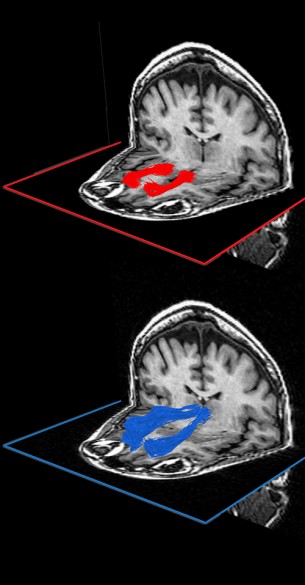

A brain-mapping study, published in the April 11 issue of The Journal of Neuroscience, has found that people’s ability to make decisions in novel situations decreases with age and is associated with a reduction in the integrity of two specific white-matter pathways that connect an area in the cerebral cortex called the medial prefrontal cortex with two other areas deeper in the brain.

The critical white-matter connections that the experiment identified run from the thalamus, a highly connected relay center in the brain, to the medial prefrontal cortex, an area of the brain involved with decision making, and from the medial prefrontal cortex to the ventral striatum, which is associated with the emotional and motivational aspects of behavior.

On the same day, the participant’s brains were scanned using a relatively new MRI technique called diffusion tensor imaging (DTI). In the last 20 years, most brain imaging research has been done with fMRI, an imaging method that measures variations in the oxygen consumption in different areas of the grey matter, which correspond to variations in neuron activity levels. By contrast, DTI detects the water trapped by the myelin sheaths that surround the axons in white-matter regions and produces a signal related to the density, diameter and amount of myelination of the axons (a combination the researchers call ‘integrity’).